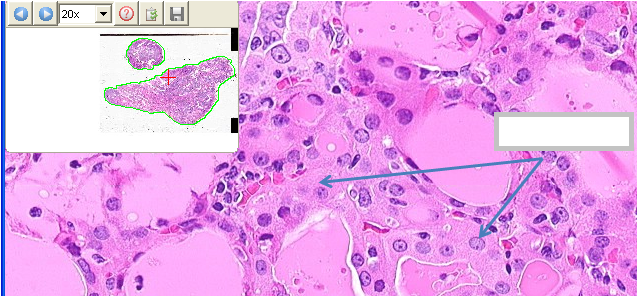

What cell type is the top arrow pointing to? What about the bottom arrow?

Follicular cells

C cells

What cell type is the arrow pointing to?

Oncocytic cell / Hurthle cell

What are characteristic features of oncocytic / Hurthle cells?